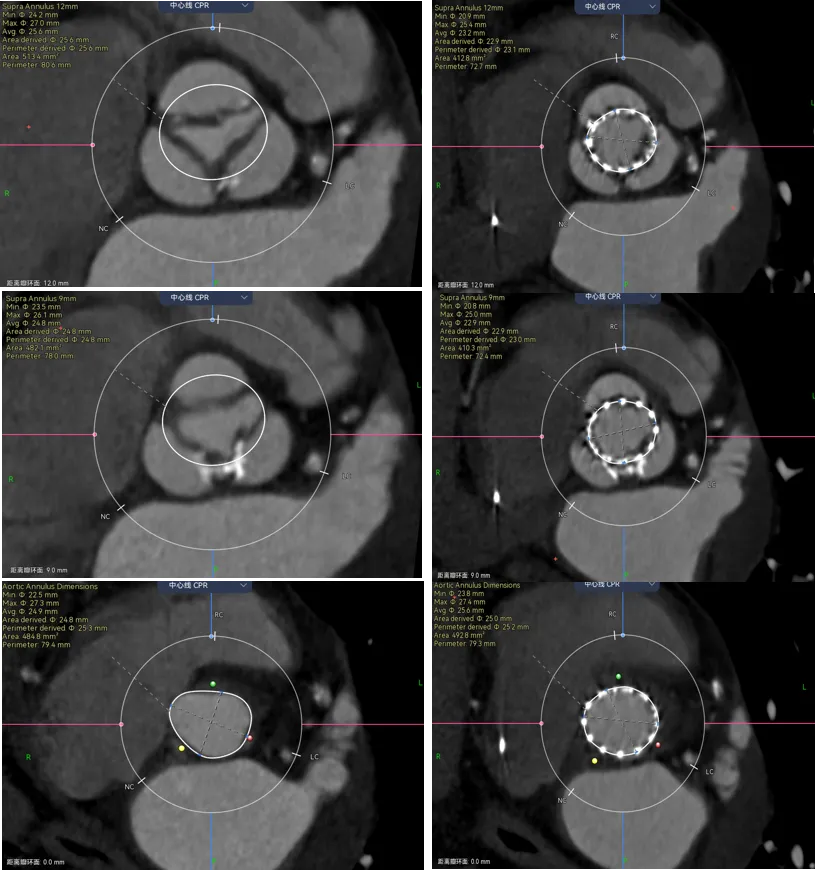

举个例子,以下3个病人,都是Type0二叶瓣,植入进去以后一个瓣膜往右偏,一个瓣膜往左偏,一个瓣膜正在中间。画的时候要怎么判断呢?

病例1 - 钙化集中在大弯侧,将瓣膜像小弯侧推挤,单边钙化要注意识别冠脉风险,并不是二叶瓣就没有冠脉风险了。可以看到图中的瓣膜距离冠脉开口很近。

病例2 - 钙化集中在小弯侧,将瓣膜向大弯侧推挤,(此类的冠脉就比较安全,可以类比到Type1型的LR融合)

结合下图术后CT可以看到,我对瓣膜位置的预判基本正确,钙化与升主的限制共同把瓣膜推向小弯侧,这时候可以看到瓣膜距离冠脉开口非常之近,如果再贴近一点,瓣膜植入再高一点,裙边或者吊桥可能会有冠脉阻挡风险。所以像这种单边钙化的冠脉风险也是需要看看的。

让我们来看看术前和术后预测的对比,预留的交界区域完全正确,瓣膜无法填满三个瓣叶的交界边缘,从瓣环到瓣上12mm都留有一丝缝隙,这类病例除非充分后扩贴一贴,不然多少都会有一点儿漏,术前可以充分预估到。